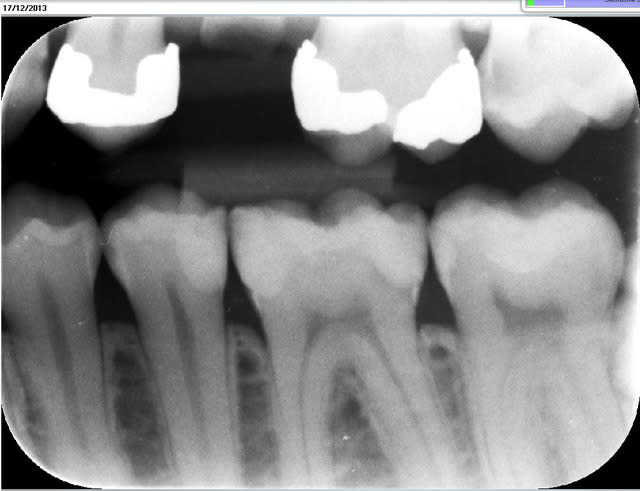

As-tu une radio du travail fini?

> As-tu une radio du travail fini?

Non, je n'irradie pas mes patients pour vérifier mes composites ;) mais il revient pour l'autre coté, je ferais la radio ;)

la radio et la photo a 1 mois

Faut avouer qu'ici l'indication du composite sur la 6 est quand même un peu "couillu", en distal par contre il reste une radio clarté: carie résiduelle ou épaisseur de colle importante, en tous cas ça peut fragiliser la suprastucture.